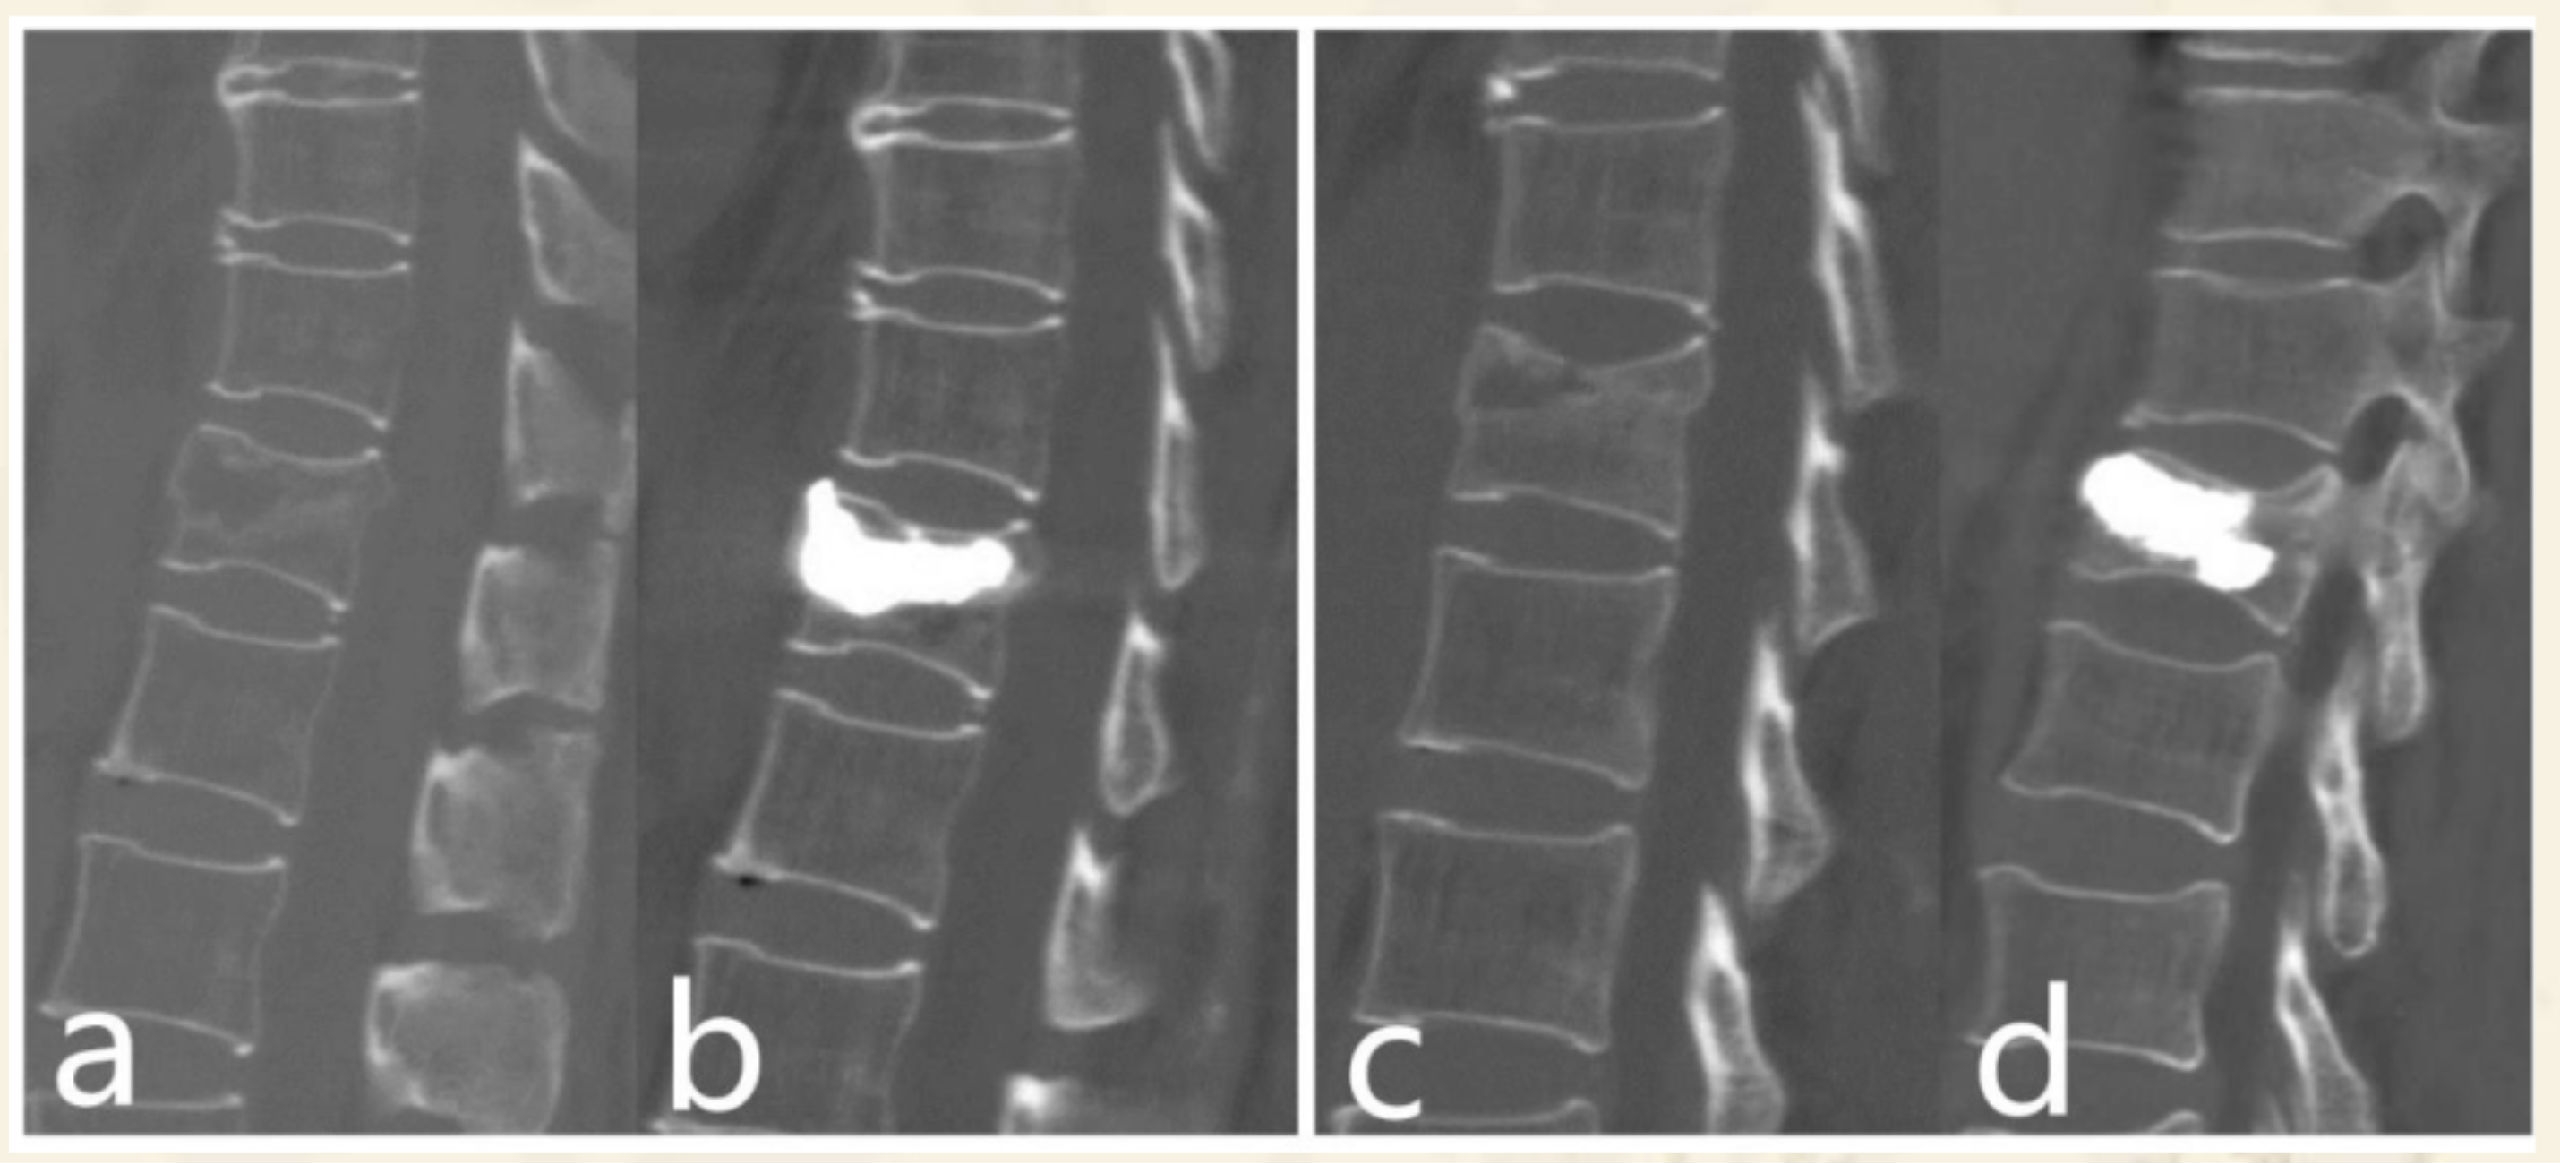

压缩后嵌插型骨折线,CT:高密度带、MRI低信号带。

压缩后自动复位裂隙型,CT:裂隙,MRI:低信号区(气体)

压缩后自动复位裂隙型

CT:裂隙,MRI:高信号区(液体)

术前CT

术后CT